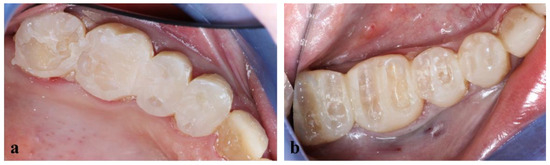

Teeth of the upper (a) and lower (b) right pre-molar and molar sectors were prepared through the mock-up as shown in Figure 8.

Figure 8.

Teeth preparation through the mock-up of upper (a) and lower (b) right premolars and molars.

Once teeth were prepared, an optical impression of the preparations was made, and a temporary resin (Structur Premium, VOCO) was placed on the teeth with silicone keys (Figure 9) to protect them for a week, the time needed for the prosthetic laboratory to prepare the fixed prosthetic components.

Figure 9.

Silicone keys made for repositioning temporary resin after teeth preparations.